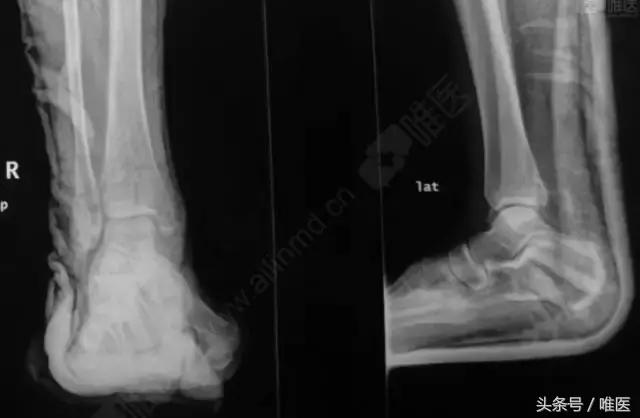

X线:右侧踝关节骨折

治疗前影像